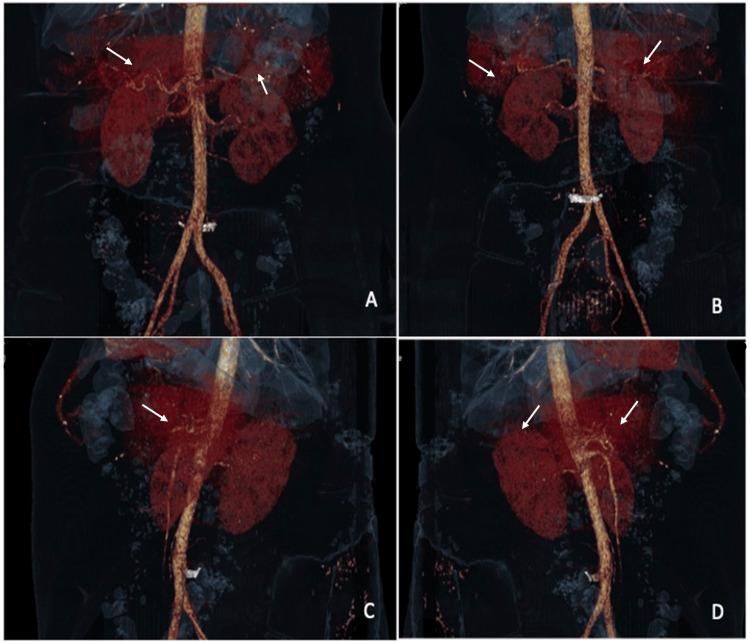

Wünderlich syndrome (WS) is an unusual clinical condition defined by spontaneous perirenal space hemorrhage or subcapsular renal hemorrhage without antecedent of traumatic history, often triggered by various factors. It manifests mainly as abdominal pain and fever. As the signs and symptoms are nonspecific, imaging studies are essential for diagnosing and ruling out differential diagnoses. We present a case of a 42-year-old female with no previous pathological or traumatic history, who was admitted with abdominal pain and episodes of fever, attributed to bilateral spontaneous renal hematomas. We conducted a comprehensive clinical history to rule out metabolic, autoimmune, infectious, traumatic, or congenital factors. Laboratory tests for autoimmune, infectious, coagulation, and metabolic causes were all negative. An abdominal contrast-enhanced computed tomography revealed a bilateral renal hemorrhage, ruling out other abdominal causes of pain and confirming a bilateral WS. The patient underwent fluoroscopy-guided drainage and biopsy because we did not have an accurate diagnosis based on the imaging reports, which indicated either pure hematomas or renal abscesses. We ruled out any tumoral or infectious process with the drainage samples. After a thorough consideration and elimination of all possible causes, we arrived at the diagnosis of an idiopathic bilateral WS, an infrequent medical occurrence.